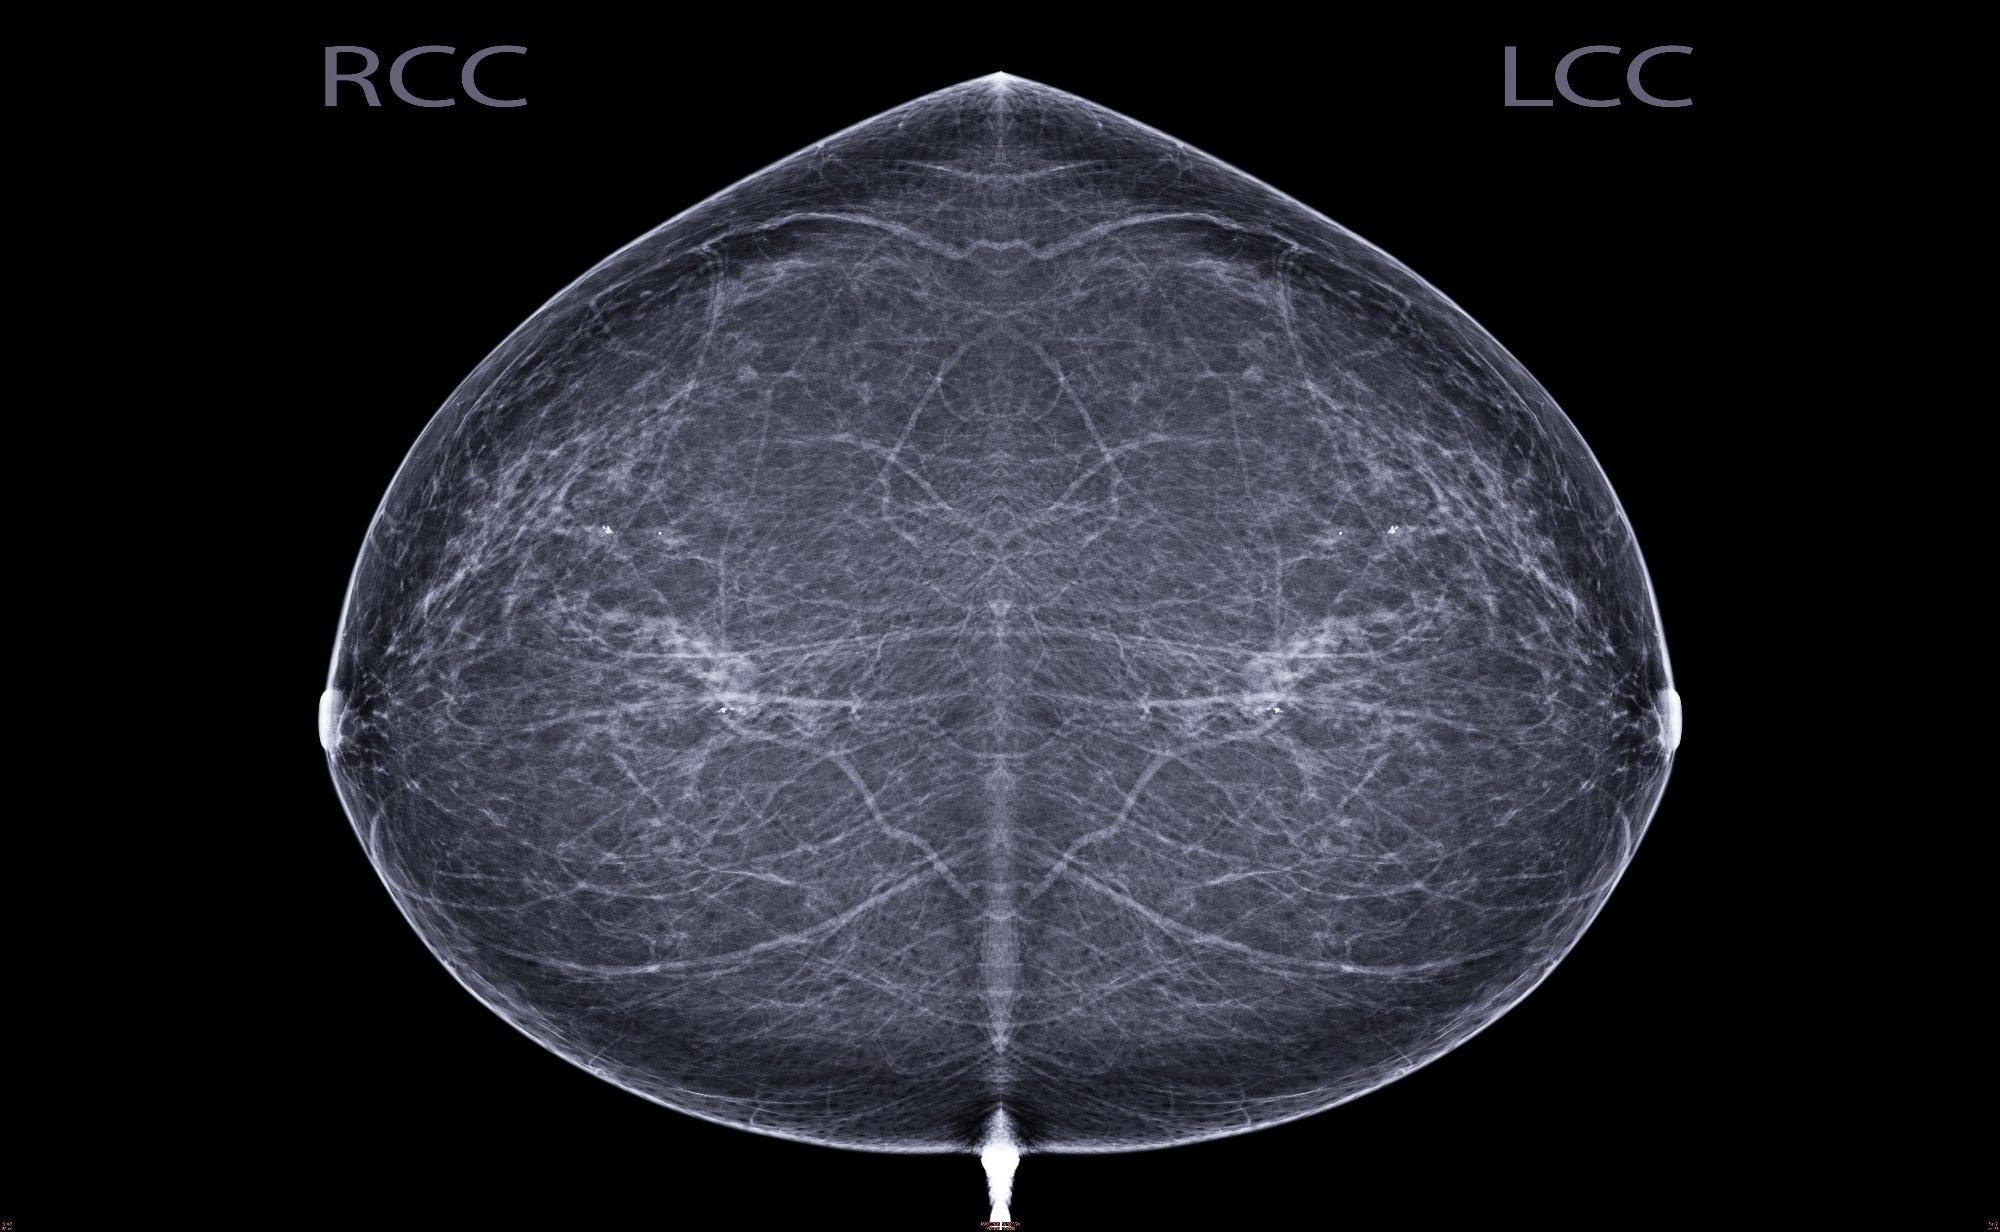

Early Indicators of the Impact of Using AI in Mammography Screening for Breast CancerStudy: Early Indicators of the Impact of Using AI in Mammography Screening for Breast Cancer. Image Credit: Radiological imaging / Shutterstock

All participants underwent standard imaging protocols with digital mammographs of craniocaudal full-field and mediolateral oblique views being captured. All the positive cases included in this study were screen-detected ductal carcinoma or invasive cancers, which were confirmed in situ using needle biopsies. Data on pathology reports, lesion size, node positivity, and diagnoses were also obtained from the country’s health registry.